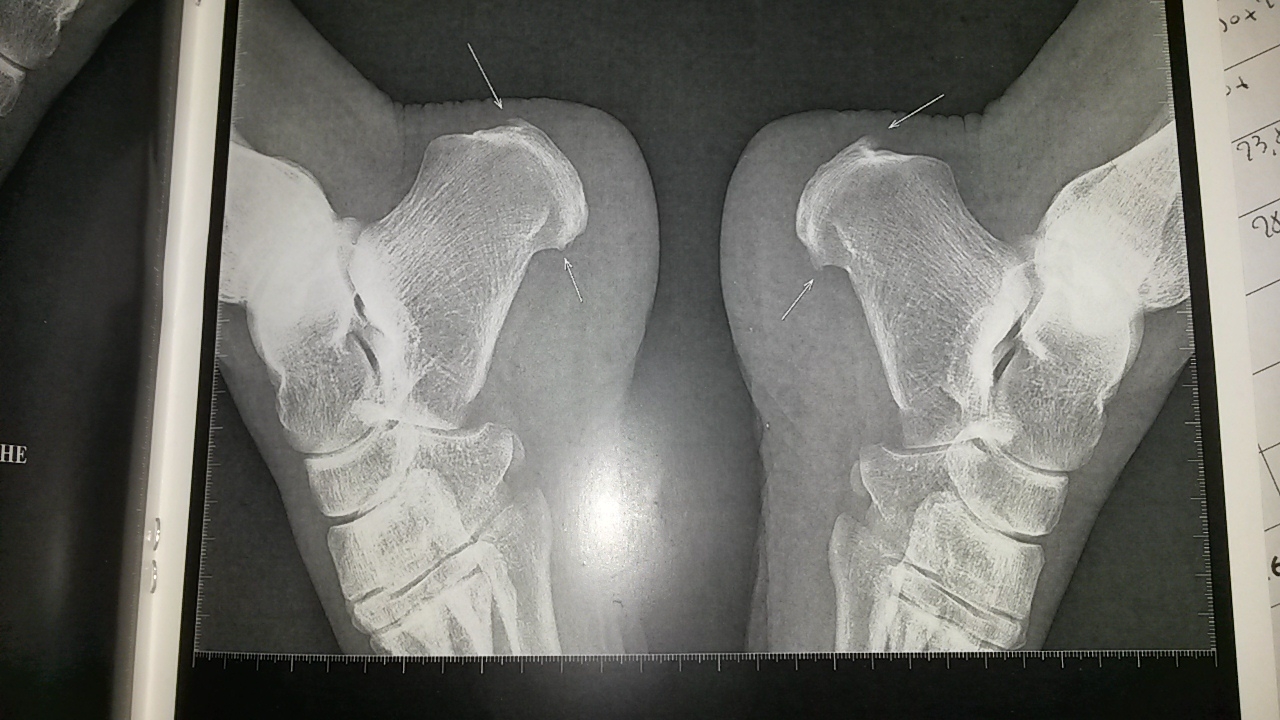

| Dire merci | ah ben je te garantie qu'en cas d'épine calcanéenne tu hurles si tu marche pieds nus car l'epine s'enfonce encore plus dans les chairs à l'interieur. sinon oui sans épines ca serait tout à fait bénéfique je pense. je vais prendre des photos de mes radios pour que vous voyez le truc |

Par oumicalin : le 18/03/19 à 10:32:23

| Dire merci | voici mes radios et contre rendus :![]() ![]() |

Par kagnotte : le 15/06/19 à 15:35:13

| Dire merci | L'épine que j'ai au pied droit est beaucoup plus importante que les tiennes, mais j'ai la chance que les ondes de chocs fonctionnent. Mais elle me rappelle à l'ordre quand même très régulièrement. Et je suis d'accord la douleur n'est pas supportable par moment. Celle du pied gauche me gène un peu mais moins. Pour les infiltrations ma rhumatologue n'a pas voulu avant de tout essayer avant, elle m'a dit que c'était très douloureux. |